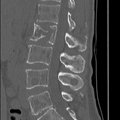

בלון kyphoplasty הוא הליך זעיר פולשני שנועד לתקן שברי דחיסה בחוליות על ידי צמצום וייצוב השבר. הוא מטפל בשברים פתולוגיים של גוף החוליה עקב אוסטאופורוזיס, סרטן או נגעים שפירים.

Percutaneous Vertebroplasty (PVP) או Vertebroplasty Vertebroplasty (PKP)

עמוד השדרה הוא אחד האתרים השכיחים לגרורות בעצמות של גידולים ממאירים, וגרורות בגוף החוליה שכיחות יותר. הרס עצם הנגרם על ידי גידולים גרורתיים מוביל לעיתים קרובות להתמוטטות חוליות או לעיוות, דחיסת חוט השדרה, שברים פתולוגיים, היפוקלצמיה והיפרפראתירואידיזם משני, הגורם לכאבים קשים ותפקוד לקוי, המשפיעים בצורה רצינית על איכות החיים של החולים, כדי לקצר את משך החיים.

טיפול סימפטומטי קונבנציונלי כולל משככי כאבים בפה, הקרנות פליאטיביות, ניתוחים וטיפול סיסטמי כגון ביספוספונטים. מטופלים רבים נאבקים בטיפולים אלו עקב ביקורים חוזרים, יעילות ירודה ותופעות לוואי. בשנת 1984, המנתח הצרפתי Galibert דיווח על יישום הזרקת מלט עצם דרך עורית בטיפול בכאב בלתי פתיר הנגרם על ידי המנגיומה השנייה של עמוד השדרה הצווארי, ויצר תקדים להזרקת מלט עצם עורית זעיר פולשנית בטיפול בנגעים בחוליות. תוך 48 שעות לאחר ניתוח ורטרופלסטיה מלעורית (PVP) או קיפופלסטיקה בלון מלעורית (PKP), הקלה משמעותית בכאב הייתה קשורה להפחתת השימוש בתרופות ולשיפור הפרמטרים התפקודיים.